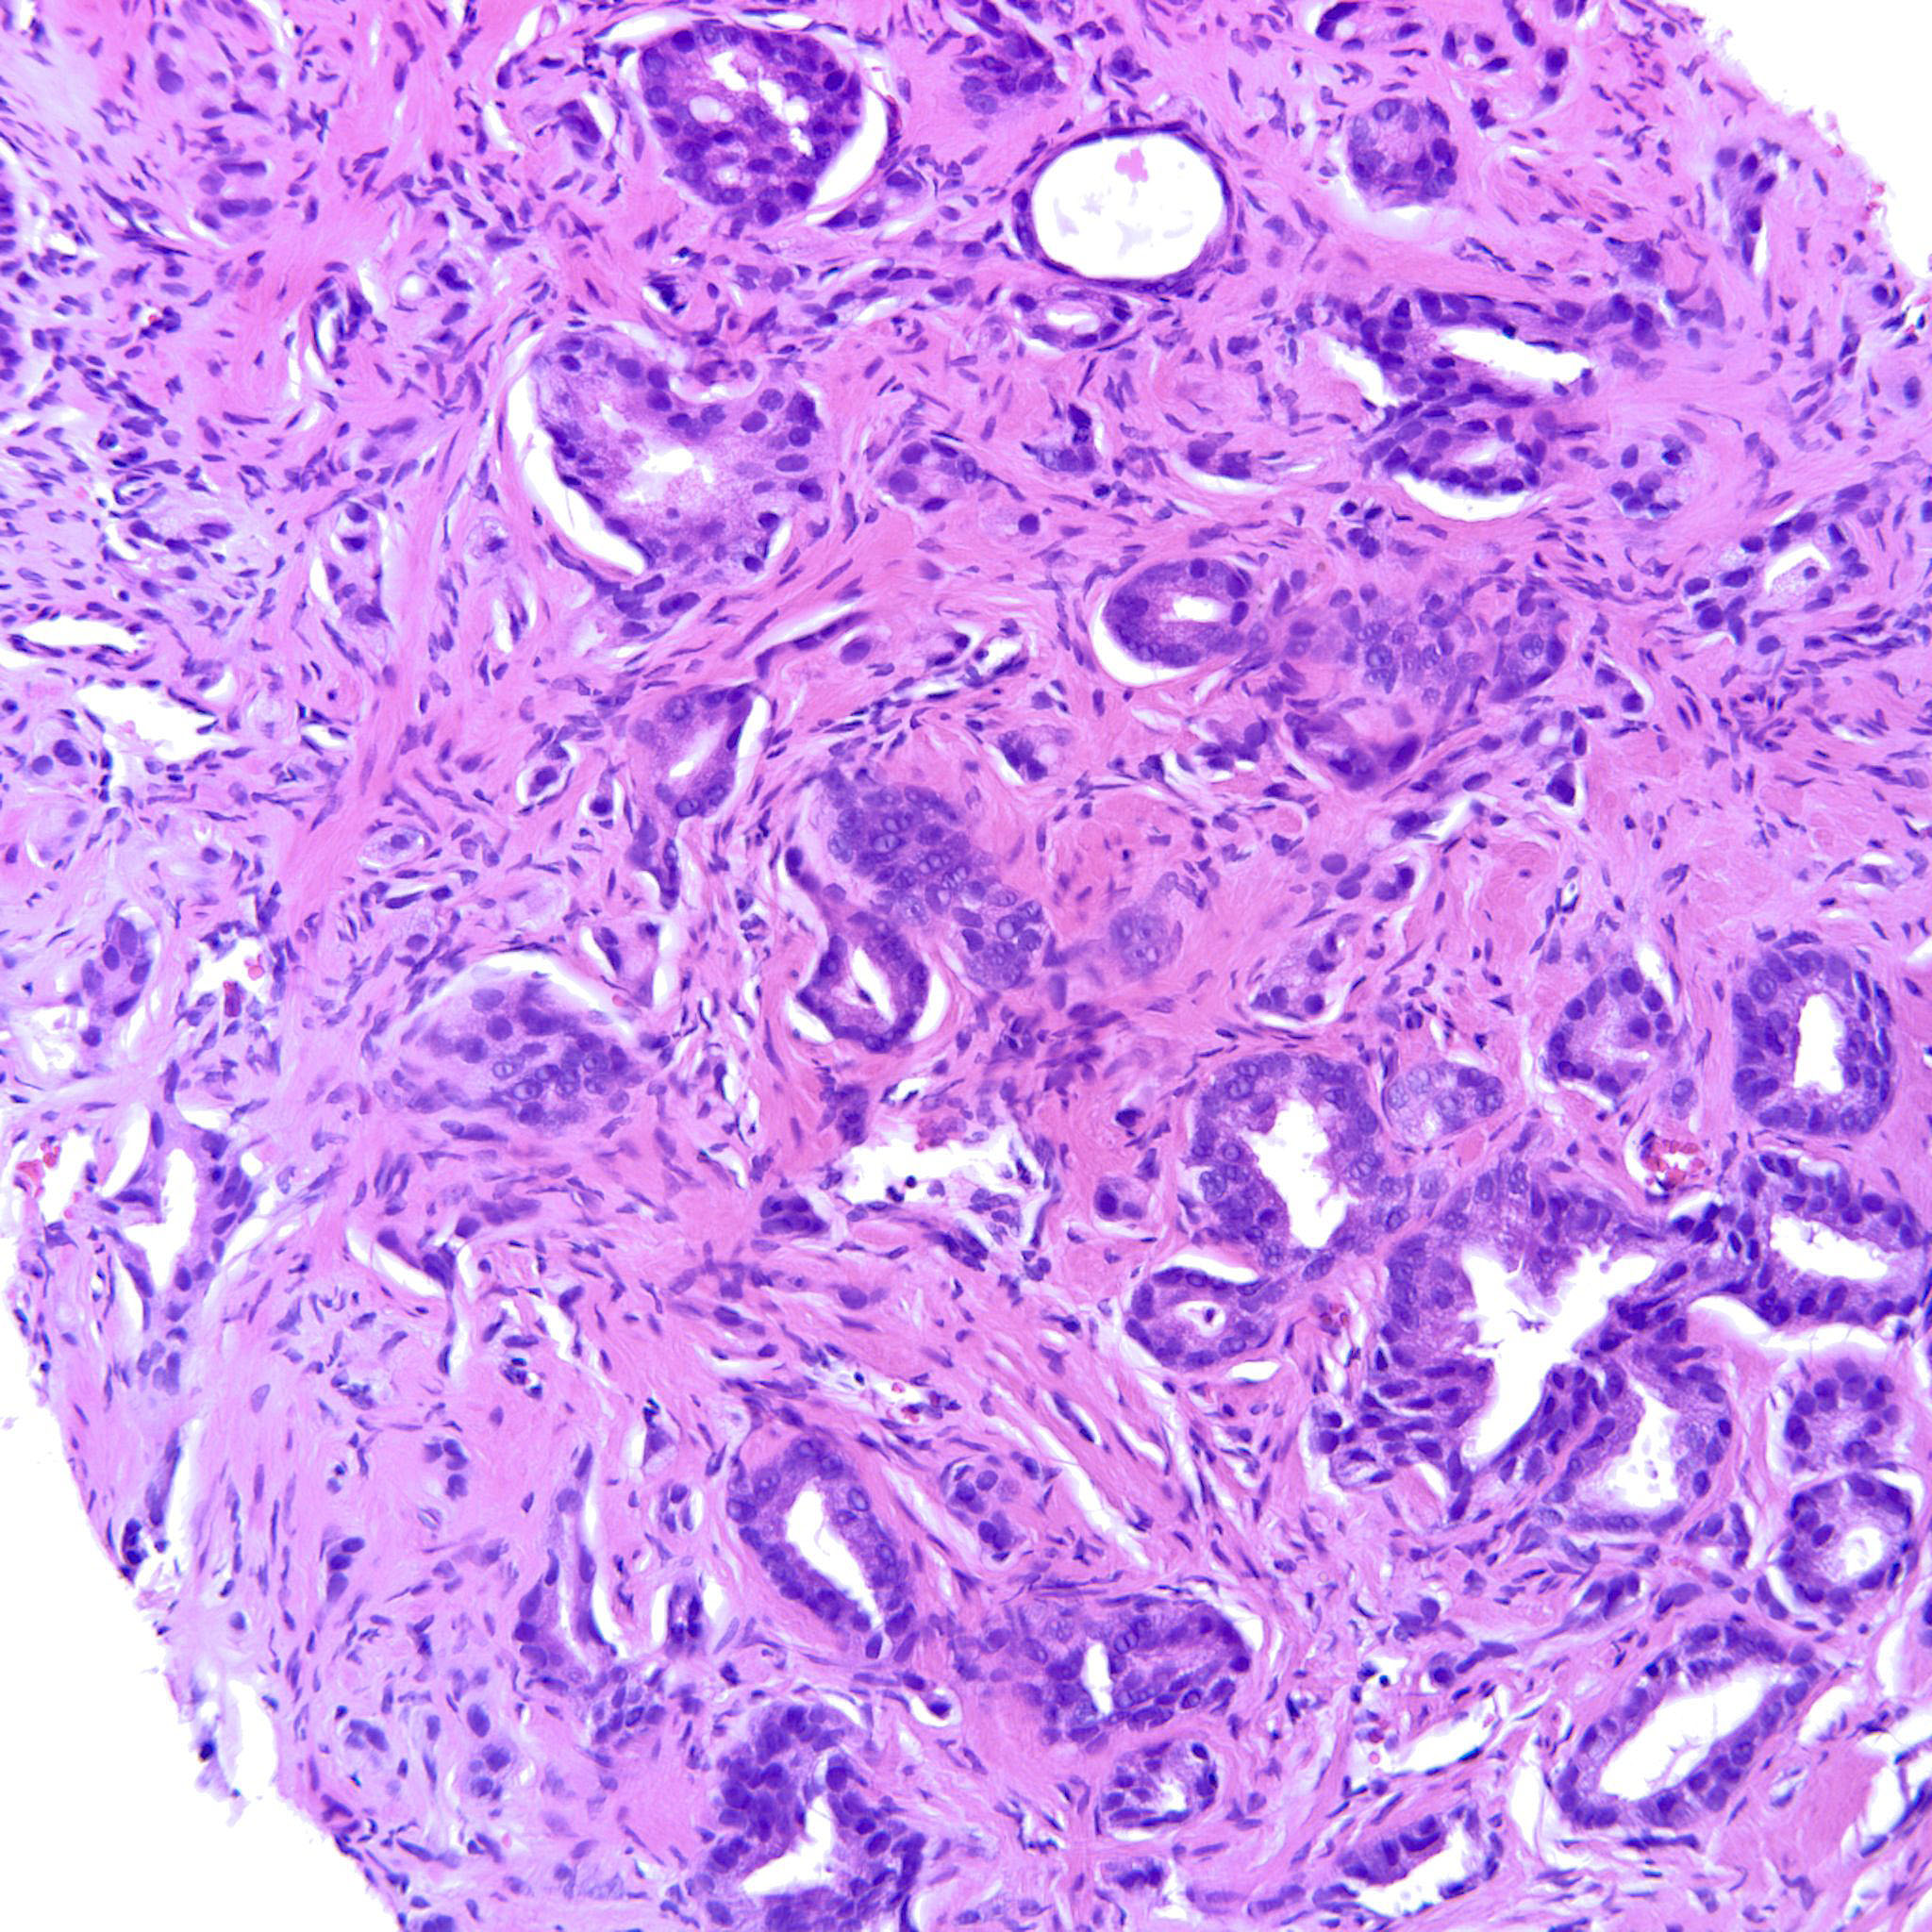

Prostate cancer grading

Case ID: 193